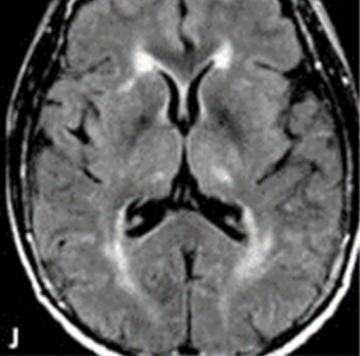

- В аксиальной плоскости. При ЗСОНМ двусторонние глубокие поражения белого вещества таламуса.5

МРТ в аксиальной плоскости при ЗСОНМ демонстрирует двусторонние сливные глубокие поражения таламуса5